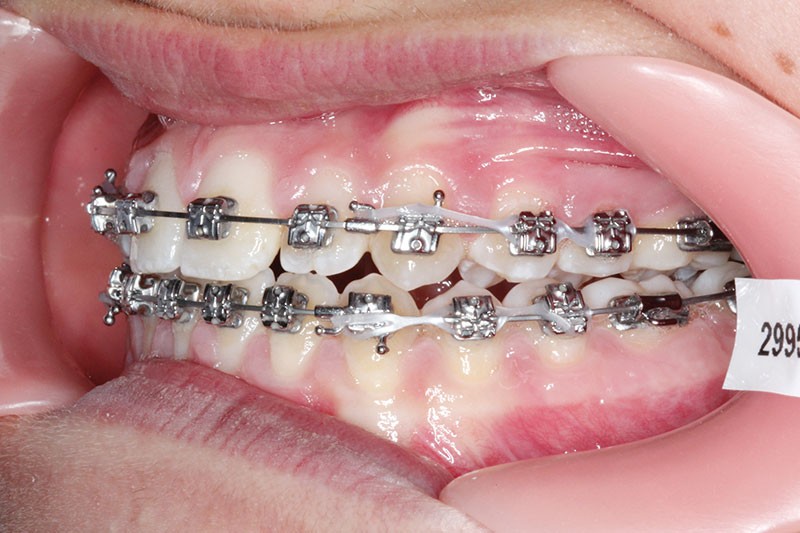

2e phase : mise en place du système multibague Carriere SLX (fig. 7 à 9)

Nous continuons le port des élastiques…